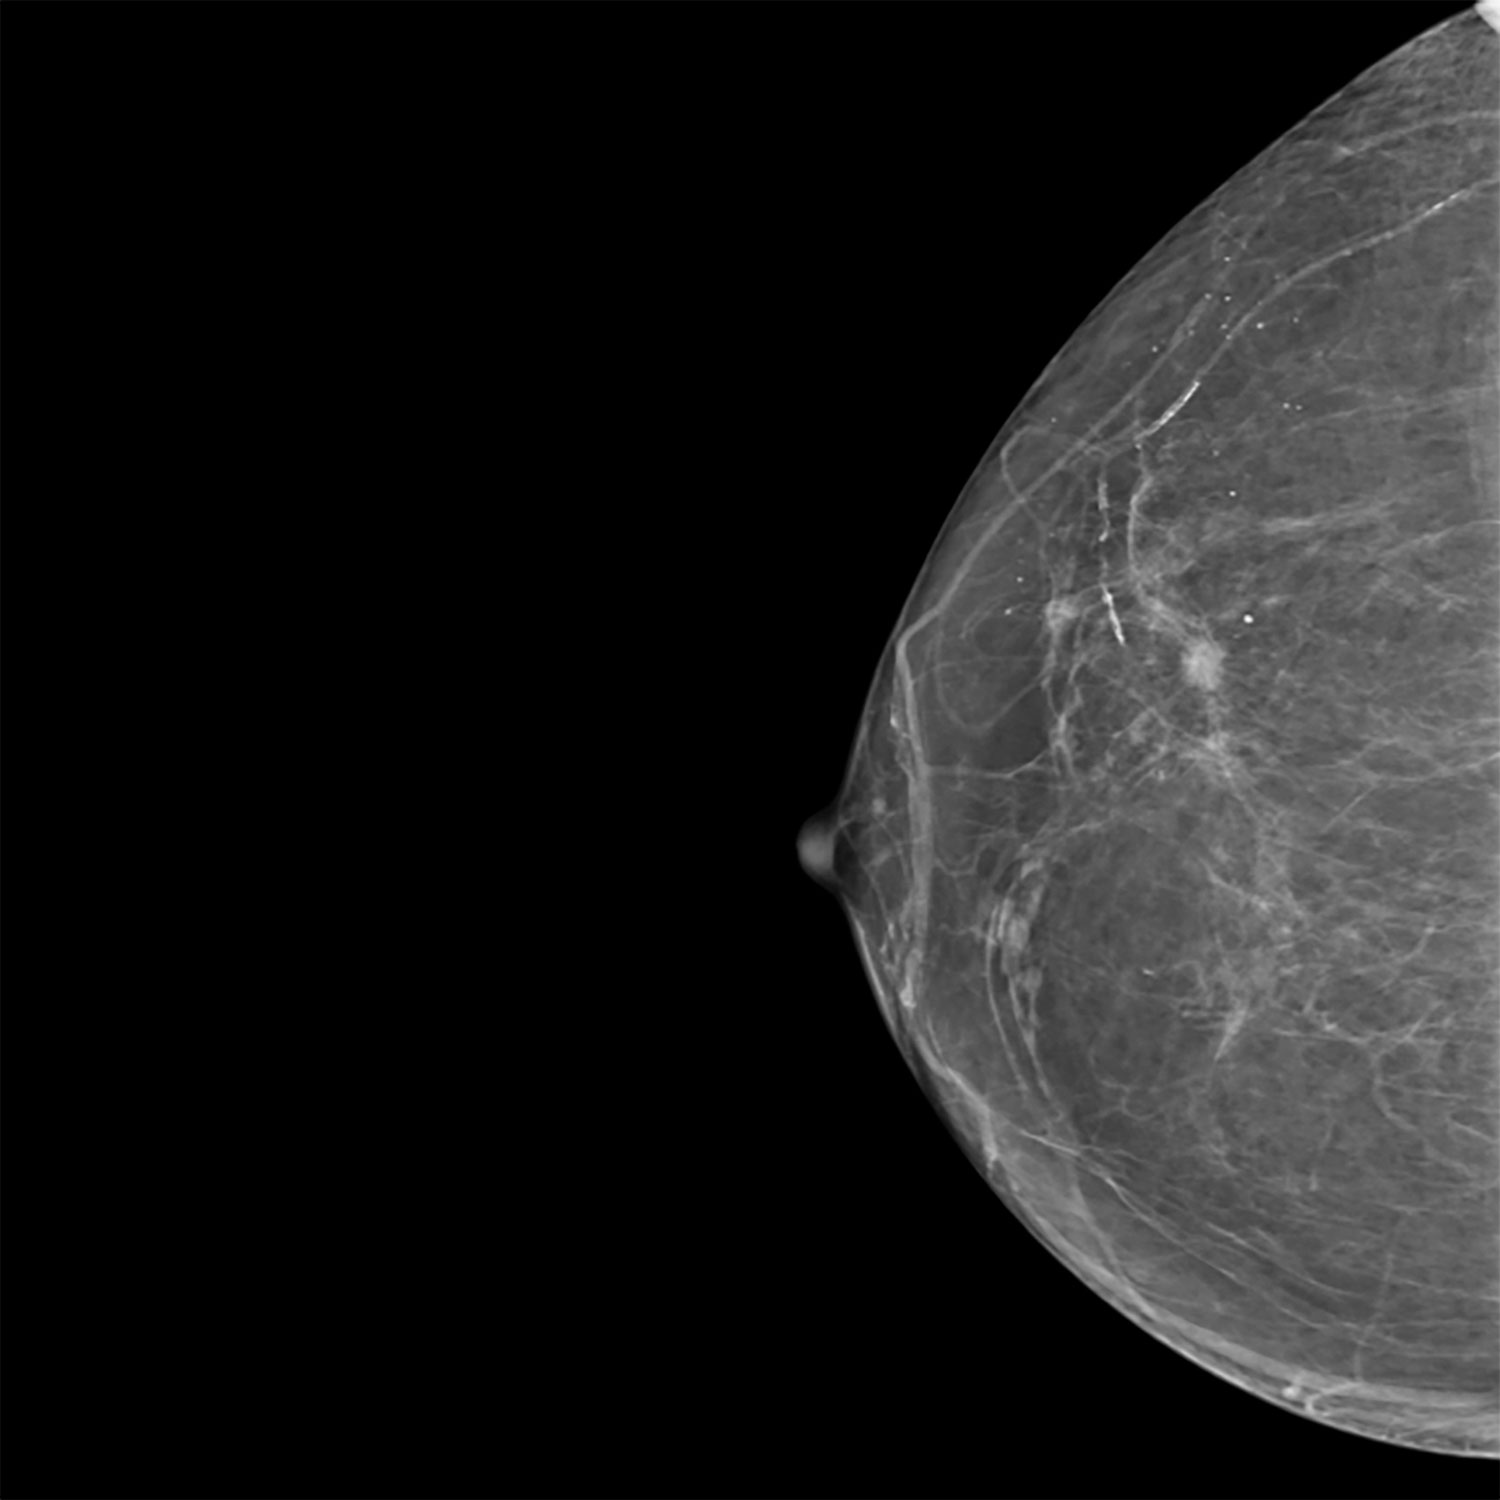

La mammographie est une imagerie radiologique utilisant des rayons X à faible dose, étant optimisée par les technologies les plus récentes, pour analyser la structure interne du sein.

Elle contribue à dépister ou à évaluer une anomalie clinique (masse palpable, douleur, modification cutanée, écoulement mammaire).

L’examen permet d’identifier et de caractériser des lésions bénignes ou suspectes.

Il peut être complété par une tomosynthèse, acquisition 3D améliorant la détection et la localisation des anomalies, ainsi que par une échographie ou une biopsie si nécessaire.